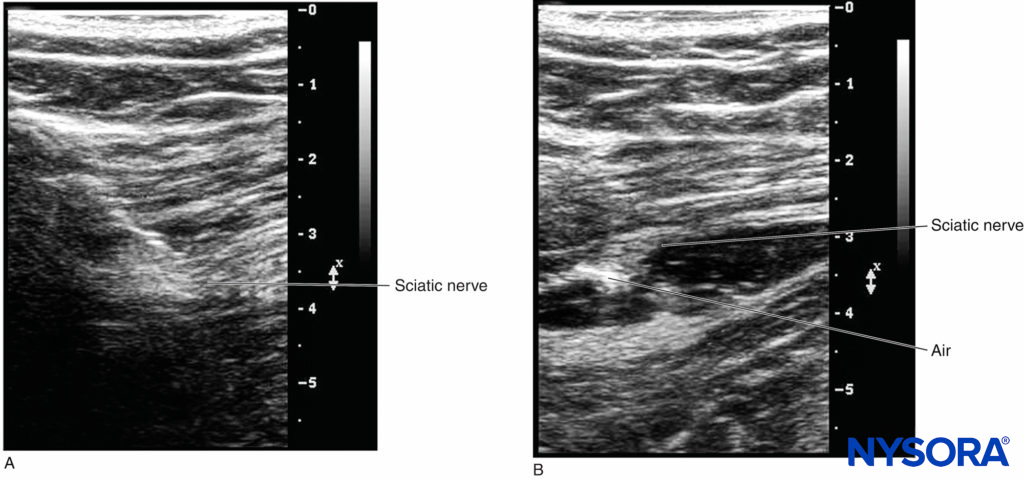

However, when the catheter is inserted 3–5 cm past the needle tip, the needle, nerve, and catheter are never in the same plane of the ultrasound beam, therefore becoming challenging to image. There are two ways to confirm the catheter tip: (1) The operator can tilt or slightly slide the transducer to see a “bright dot,” which is the transverse view of the catheter. The position of the catheter tip can be detected by observing the spread of 1–2 mL injectate through the catheter, and the use of color Doppler may help visualize the spread more significantly (Figures 8A and 8B). (2) In some cases, the bright dot may not be obviously visualized or ensured; the operator has to slide the transducer within a certain distance away from the needle tip, with the distance based on the length of catheter threaded past the needle tip. Injection of 0.5 mL air can be beneficial to ascertain the position of the catheter tip with a sharp echoic contrast on the ultrasound image (Figures 9A and 9B). The obvious drawback is that injection of air may degrade the image for other purposes.

FIGURE 9. A: The location of the catheter tip cannot be visualized before a small amount of air is injected. B: The discernablebrightness indicates the location of the catheter tip when 0.3–0.5 mL air is injected.